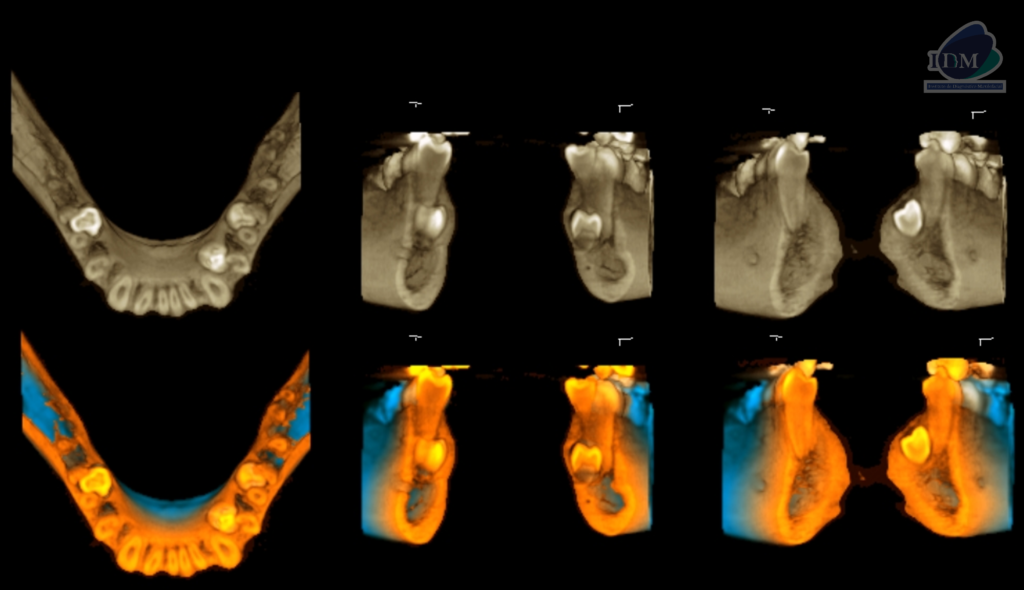

Así mismo en la tomografía volumétrica de haz se evidencia:

- Supernumerario 1: retenida en posición vertical y en contacto con los segmentos radiculares de las piezas 45 y 46, a nivel apical y orientado hacia lingual.

- Supernumerario 2: retenida en posición vertical y en contacto con los segmentos radiculares de las piezas 33 y 34, a nivel apical y orientado hacia lingual.

- Supernumerario 3: retenida en posición vertical y en contacto con los segmentos radiculares de las piezas 35 y 36, a nivel apical y orientado hacia lingual.

CORTES AXIALES

CORTES TANGENCIALES

CORTES TRANSAXIALES

RECONSTRUCCIÓN 3D

- Presencia de tres dientes supernumerarios